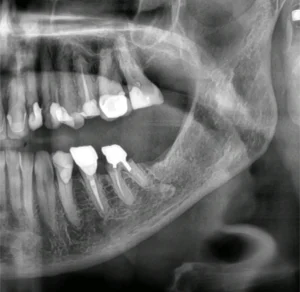

Ett nyligen utfört fall i vår klinik gällde extraktion av tand 36 (första molaren i underkäken), där vi direkt kunde placera ett implantat i samma kirurgiska seans. Resultatet blev stabilt, vävnadsbevarande och estetiskt tilltalande. Denna typ av behandling har visat sig mycket effektiv, förutsatt att rätt indikationer föreligger och att alla steg i behandlingen genomförs med kirurgisk precision.

Fall: Extraktion och direktimplantat i tand 36

I det aktuella fallet extraherades en kraftigt karierad och frakturerad tand 36. Trots viss infektion i området kunde vi efter noggrann rengöring och antibakteriell behandling placera ett implantat med utmärkt primär stabilitet (över 45 Ncm). Vi använde en flappfri teknik för att bevara blodförsörjningen till tandköttet och fyllde defekten med xenograft samt PRF.

Patienten återkom för uppföljning efter två veckor med god läkning och utan postoperativa komplikationer. Efter cirka tre månader planeras avtryck och slutlig protetik.